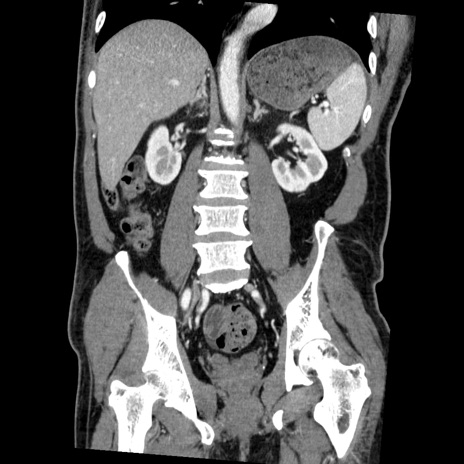

症例22(冠状断像)

【症例】50歳代男性

【主訴】腹痛

【現病歴】AVMからの被殻出血のため回復期リハ病棟入院中。 本日午後3時頃急に下腹部痛が出現した。

【既往歴】AVM、被殻出血、虫垂炎、高血圧

【身体所見】意識晴明、左半身不全麻痺、会話の理解は良好、36.5°C、腹部:膨隆、全体に板状硬、下腹部正中に圧痛点あり、反跳痛-、筋性防御不明、右下腹部にope scar

【データ】WBC 9400、CRP 0.06